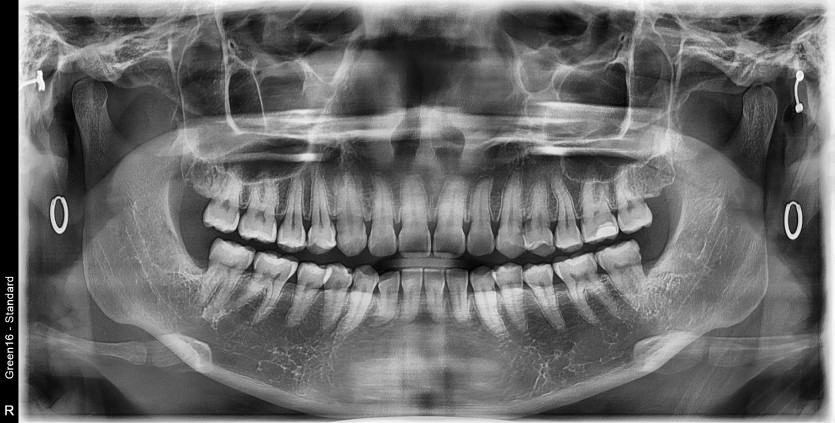

#18,28,38,48 사랑니 발치

구강 외과 전문의가 당일 발치했습니다.